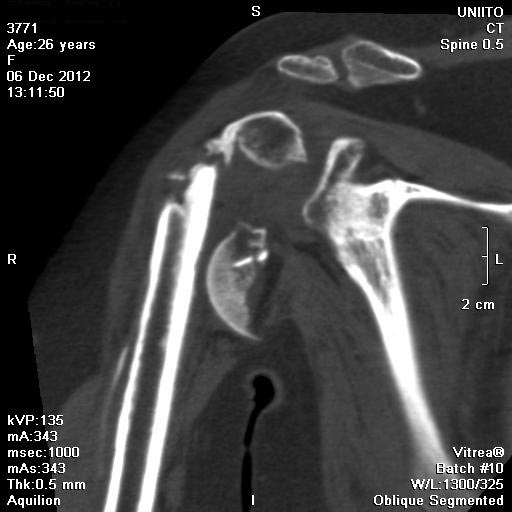

При переломах проксимального плеча, кроме обычных рентген снимков, необходимо сделать КТ исследование. Особенно 3D реконструкция, которая даст полную информацию о расположении фрагментов, потому что от количества фрагментов зависит тактика лечения. Переломы из 4х фрагментов приведет к остеонекрозу и поэтому прямое показание к эндопротезированию. Переломы с меньшим количеством фрагментов успешно могут быть синтезированы!

Из всех возможностей лечения протезирование было бы самым легким решением? и можно остановиться на hemiarthroplasty. Здесь костные фрагменты расположились разнонаправленно, и при решении на протезирование желательно сохранить большой бугорок.

Но учитывая молодой возраст, мы бы сперва провели фиксацию плеча проксимальной пластиной. Во-первых, можно собрать остатки костных фрагментов, а созданный фундамент из костей послужил бы основанием для будущих операций.

1) This a chronic, 4-part anterior fracture dislocation. How do I know it is anterior, and not posterior, only with a plain AP X-ray ??

Because posterior dislocations do not behave this way, radiographically, believe me. Also, there MAY be an A-C TYPE V dislocation in this shoulder ... But. let's forget that, now ...

A CT would be very nice, to better understand the fracture, now.